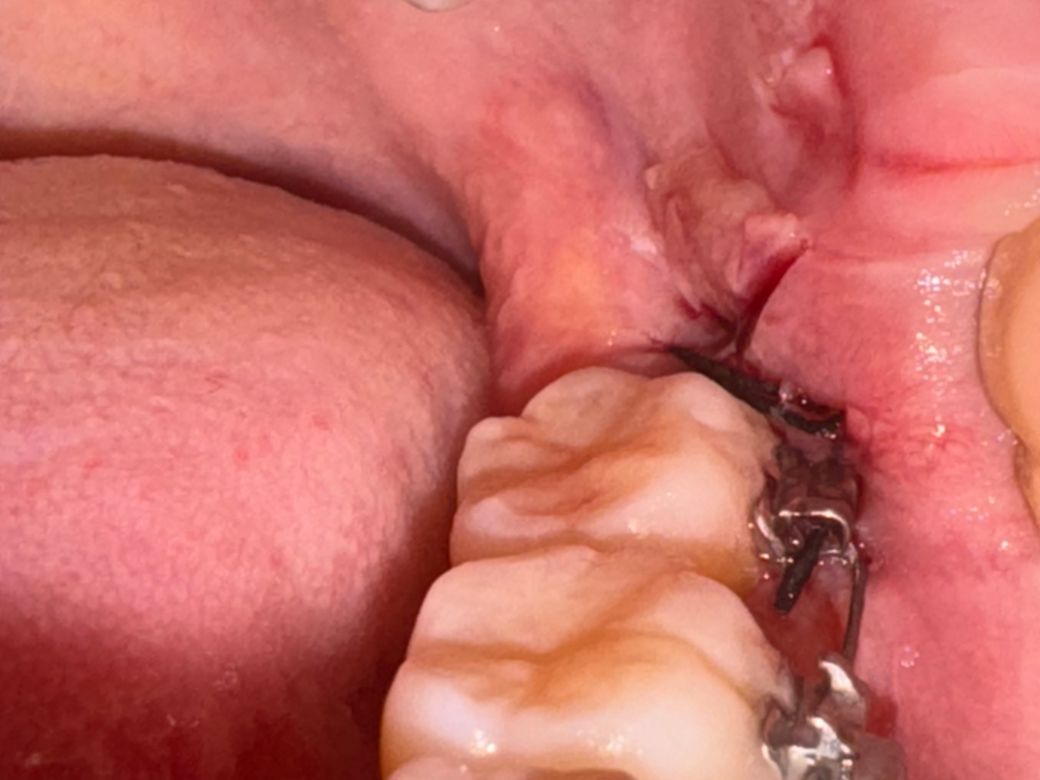

목요일 저녁에 사랑니 발치했습니다갑자기 뭔가 이물감이 들어서 음식물이 낀줄알고 거울로 보니 실빱이 교정기에 끼어있습니다..이게 실빱이 풀려서 낀건지 아니면 실빱이 길어서 낀건지 모르겠습니다 크게 아프진않은데 뭔가 불편하네요 괜찮은건가요? 얼굴이 부어서 안쪽까지 잘 보이지도 않고..병원에 가야할까요

그냥두면 됩니다. 아마도 교정지 틈새로 봉합 것으로 보입니다. 교정기 때문에 교정기 옆이나 밑으로 봉합하는 경우 종종 발생합니다.

실밥이 좀 풀려버린 것 같습니다 지혈 잘 되었다면 큰 문제는 없을 것 같습니다 불편하다면 치과가보시고 아니면 그냥 약속된 실밥 푸는날 내원하세요

잇몸에 봉합해놓은 실밥이 교정기 위에 넘어와잇는거 같습니다. 실밥을 제거하면 사라지니 너무 걱정하지마세요.